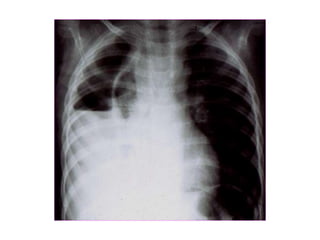

• Figure 10.18

• Chest X-ray showing a right

basal pneumonia in a previously

fit 40-year-old man with fever,

breathlessness, central cyanosis

and pleuritic pain. Chest signs

included bronchial breathing and

a pleural rub in the right lower

zone. The cyanosis was due to

the shunting of deoxygenated

blood through the consolidated

lung, the increased respiratory

rate leading to a low PaCO2

because of increased clearance

of carbon dioxide by the

unaffected alveoli. Streptococcus

pneumoniae was grown on blood

cultures.